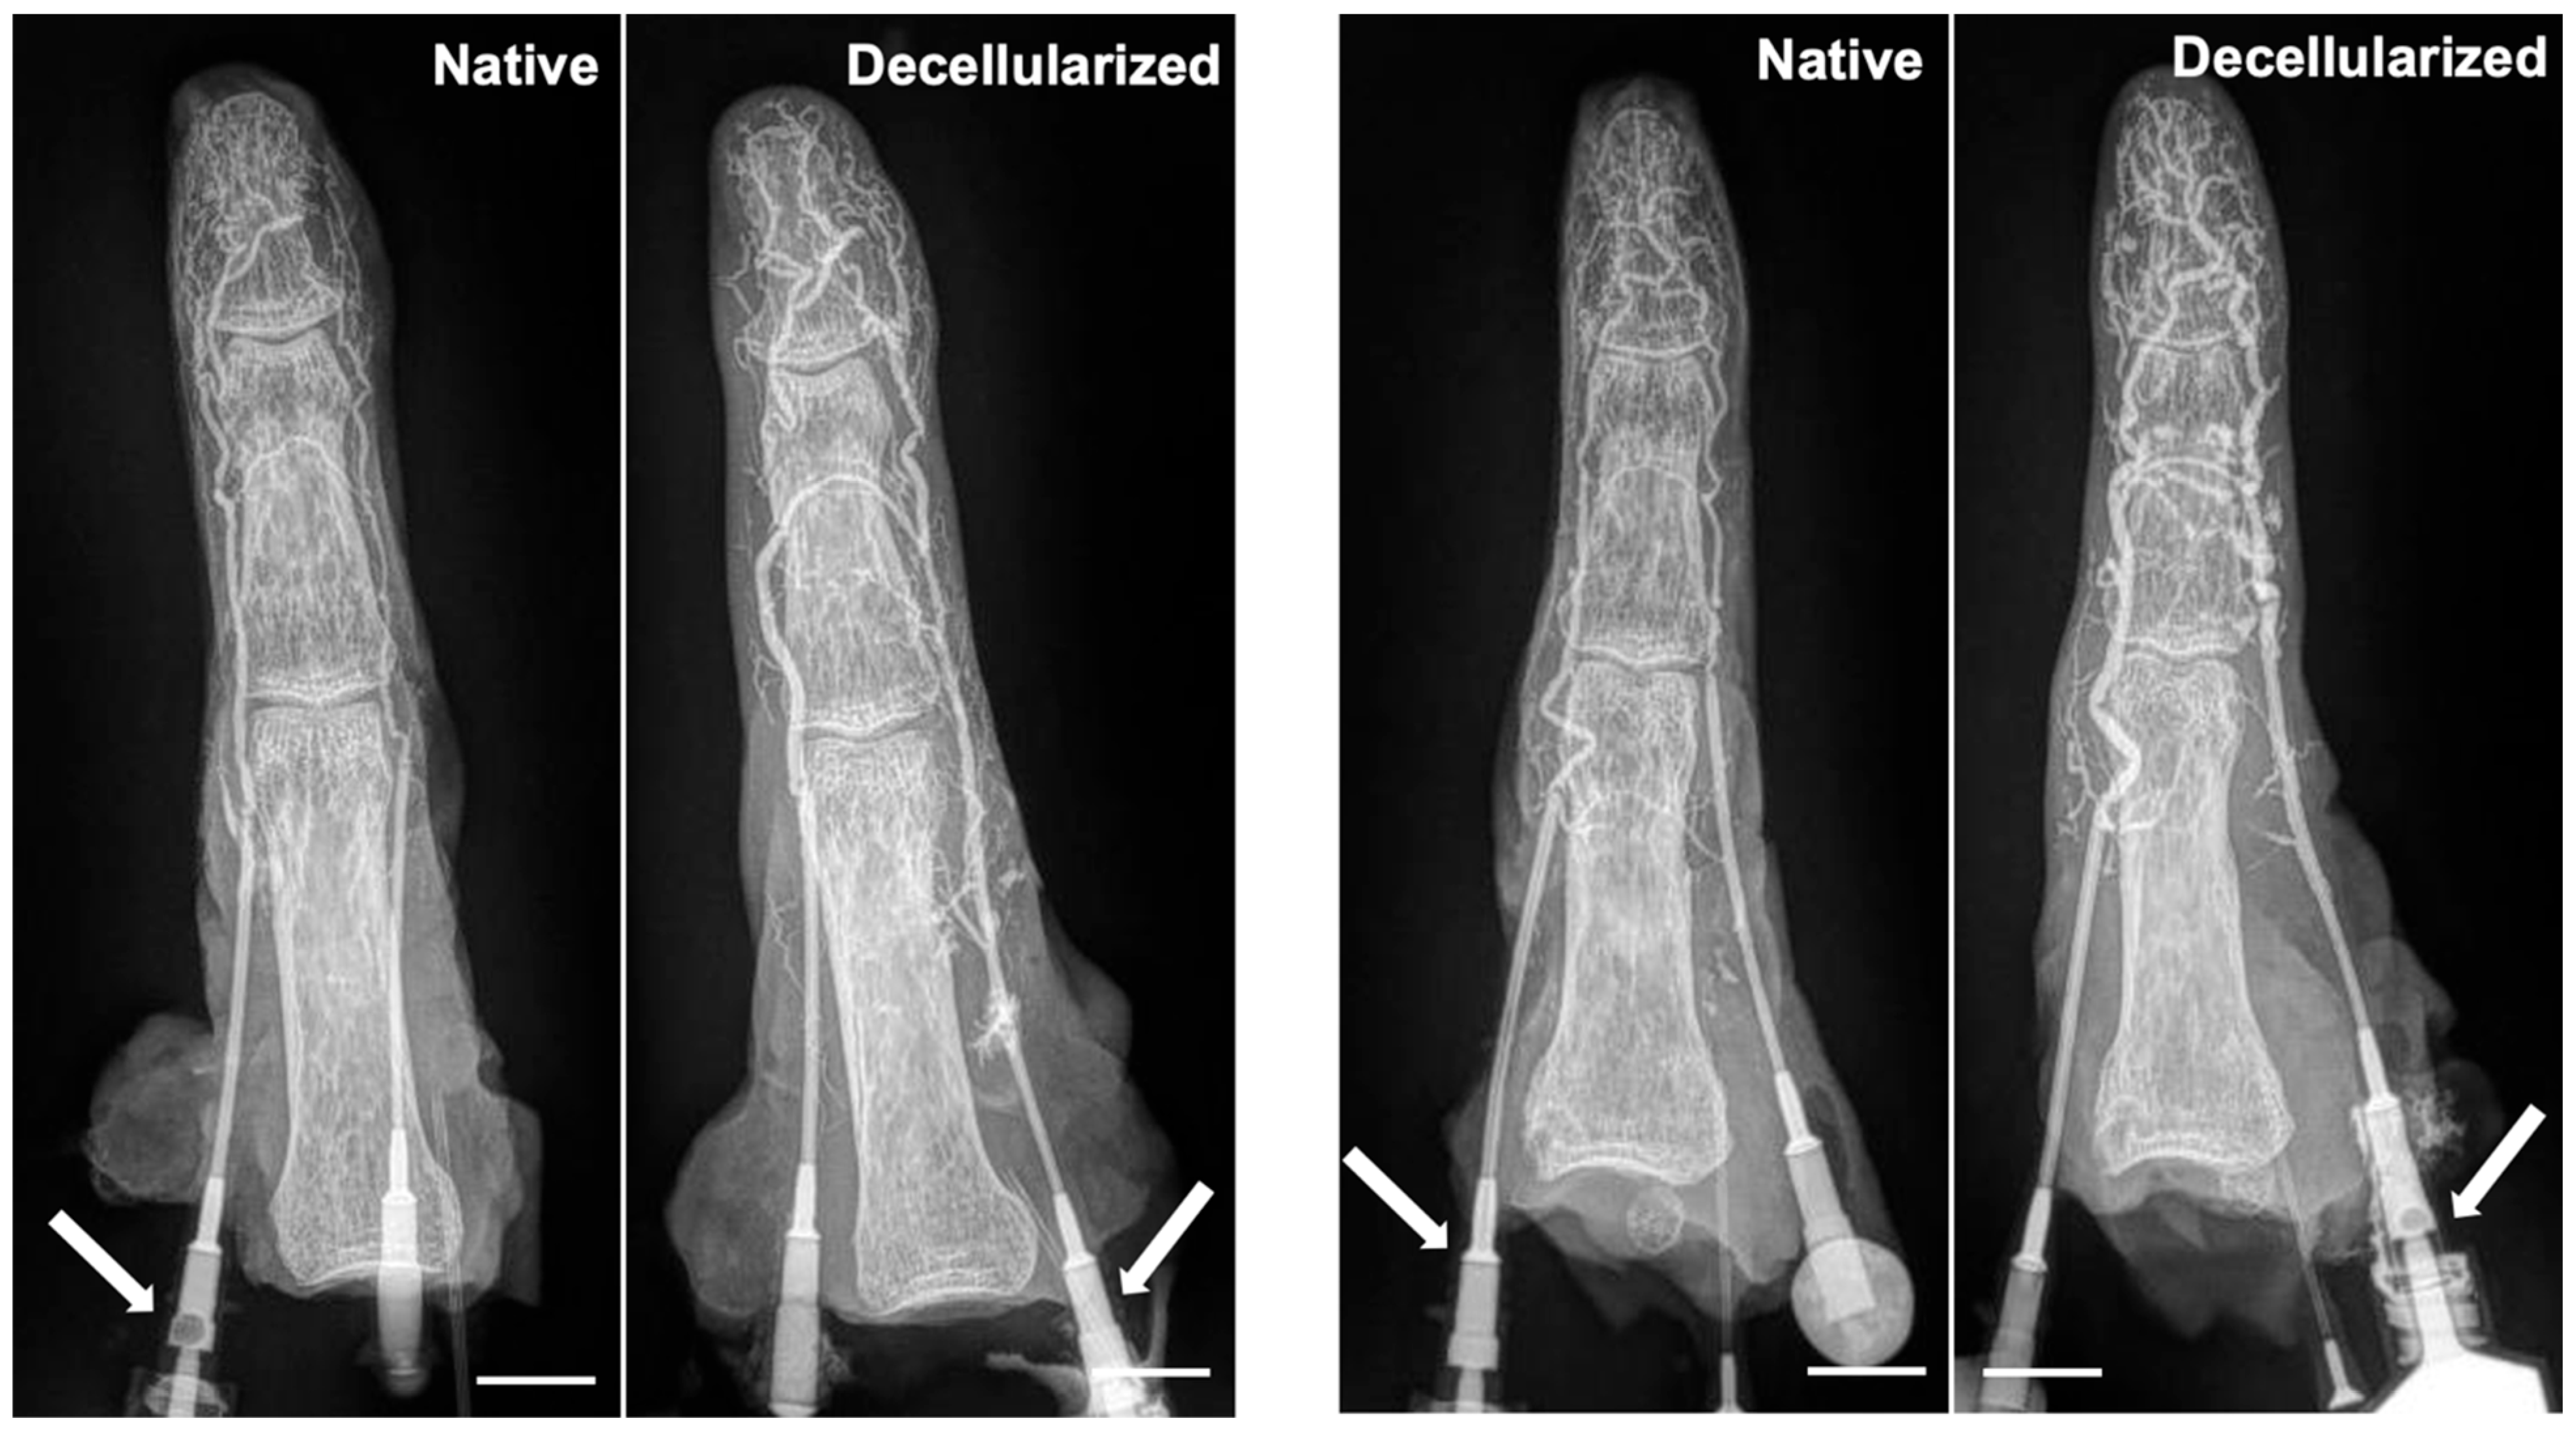

3.3. Maintenance of Vascular Network